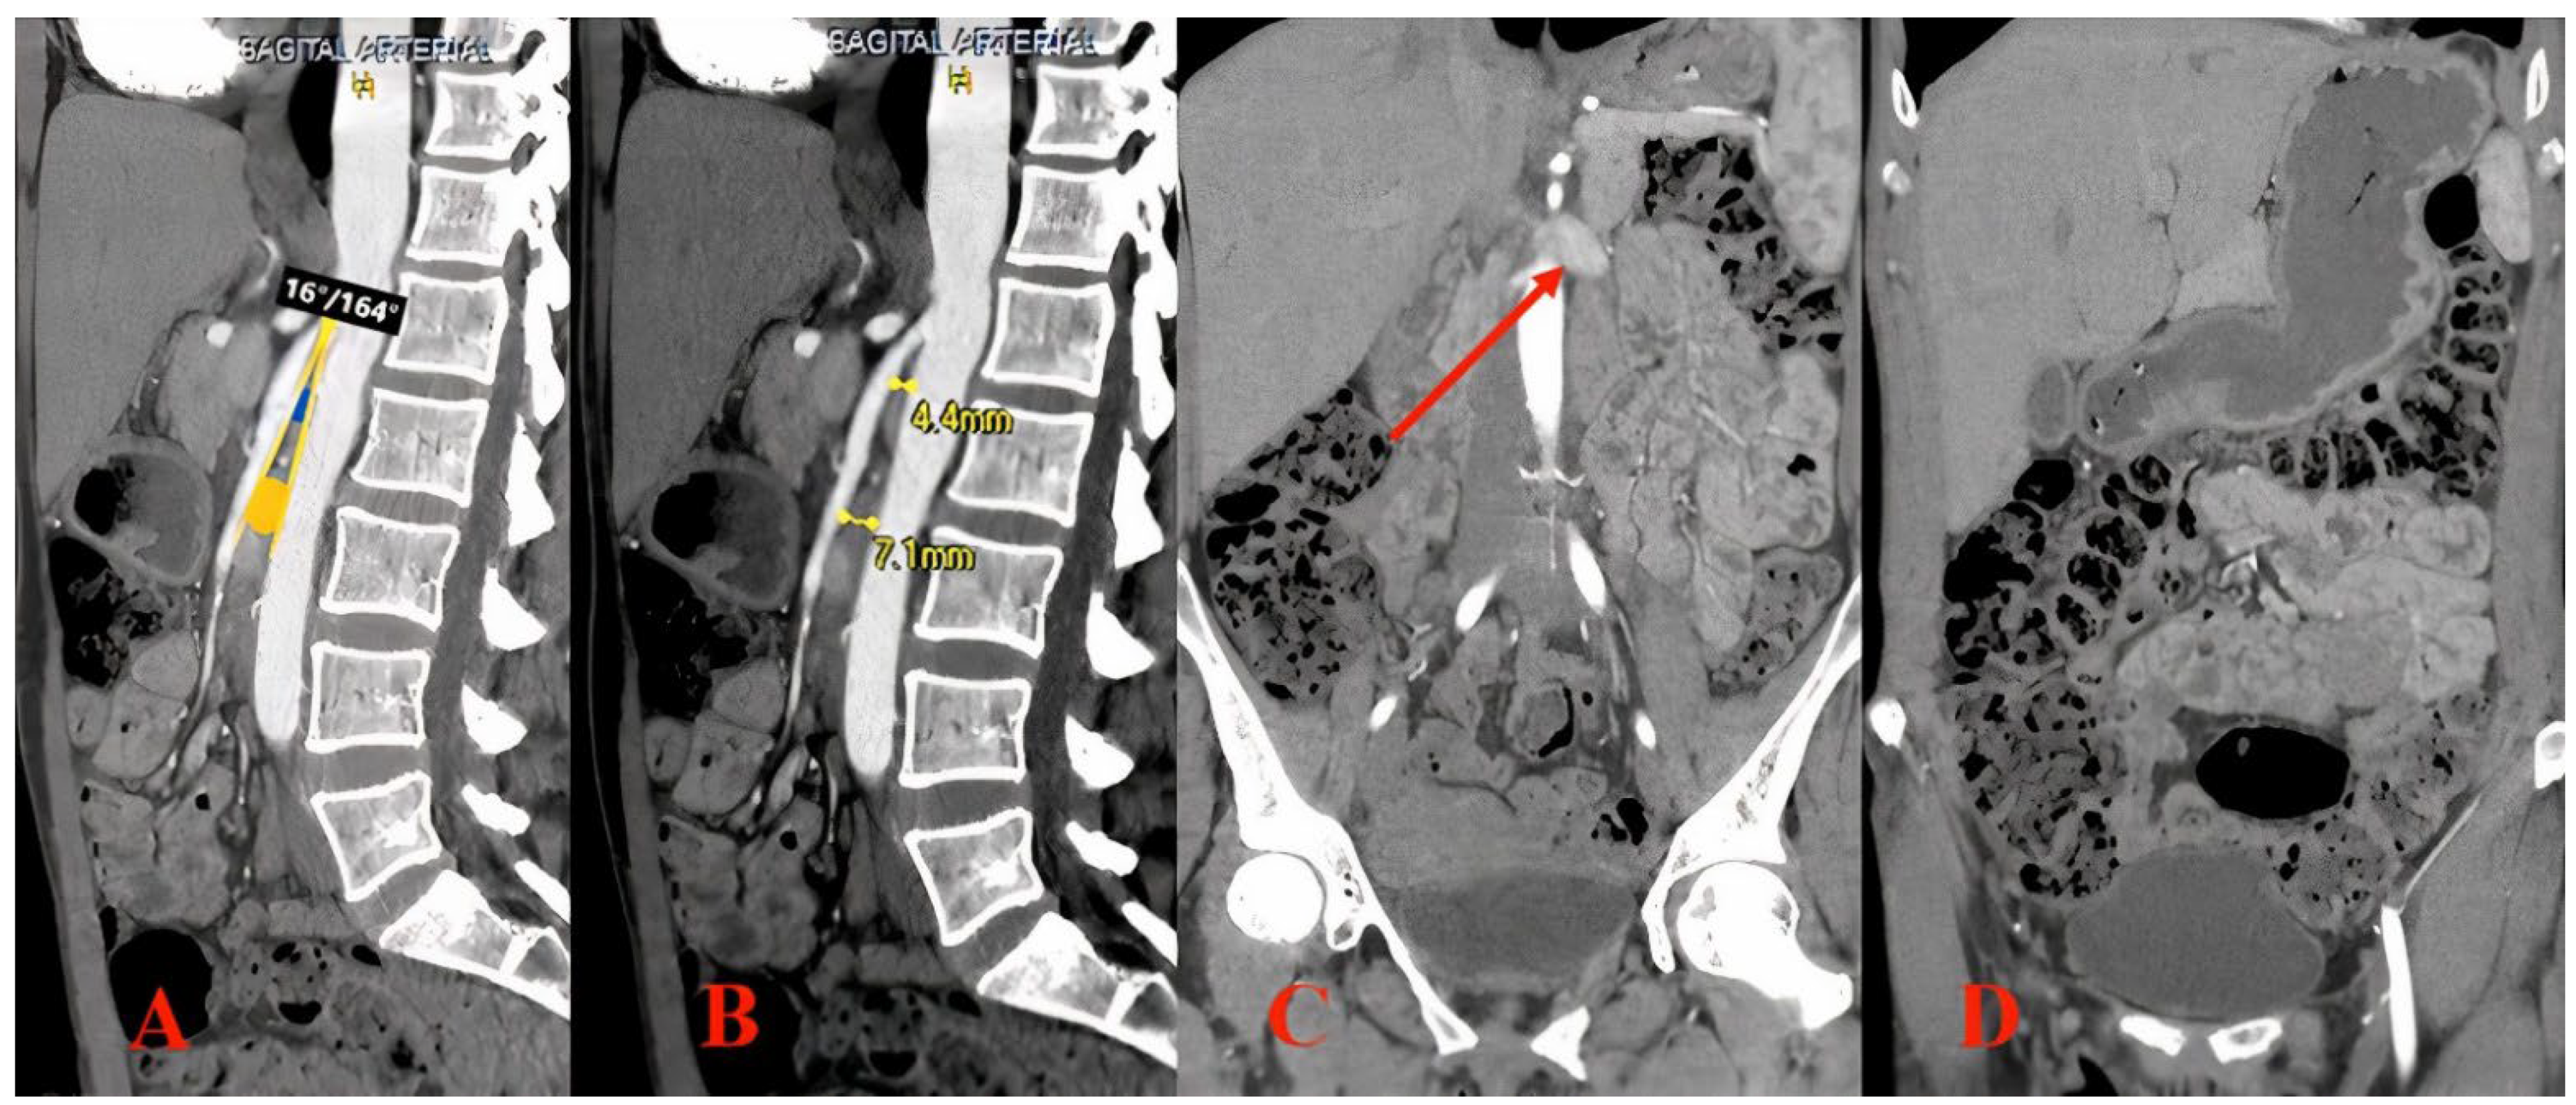

2. Imaging Diagnosis

3.1. Case Report